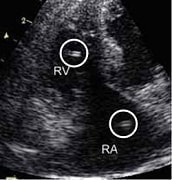

検査法④ エコー検査

エコーで心臓内を直接みることで、心臓内のフィラリアを確認します。

フィラリアがいるとエコーで『=』のように見え、検出率の高い検査です。

※心臓内のフィラリアしか発見できません。ネコちゃんでは、心臓以外(肺など)にいるフィラリアが症状を起こして問題となることが一般的です。